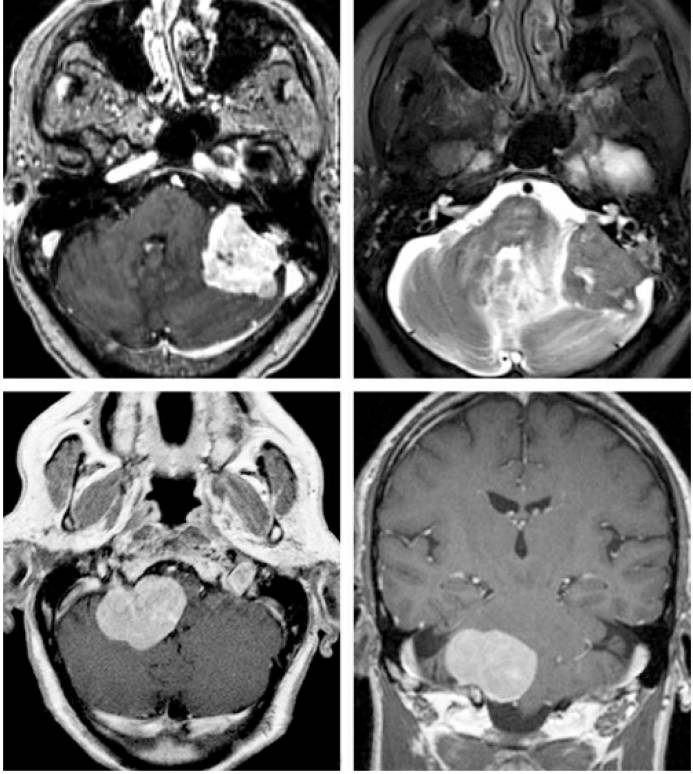

图1. 上图为一例左侧岩骨脑膜瘤或CPA脑膜瘤,肿瘤通常偏离内听道生长,且与岩骨后面的硬膜广基底相连。下图为一例右侧颈静脉孔脑膜瘤,肿瘤无明显向孔内生长。